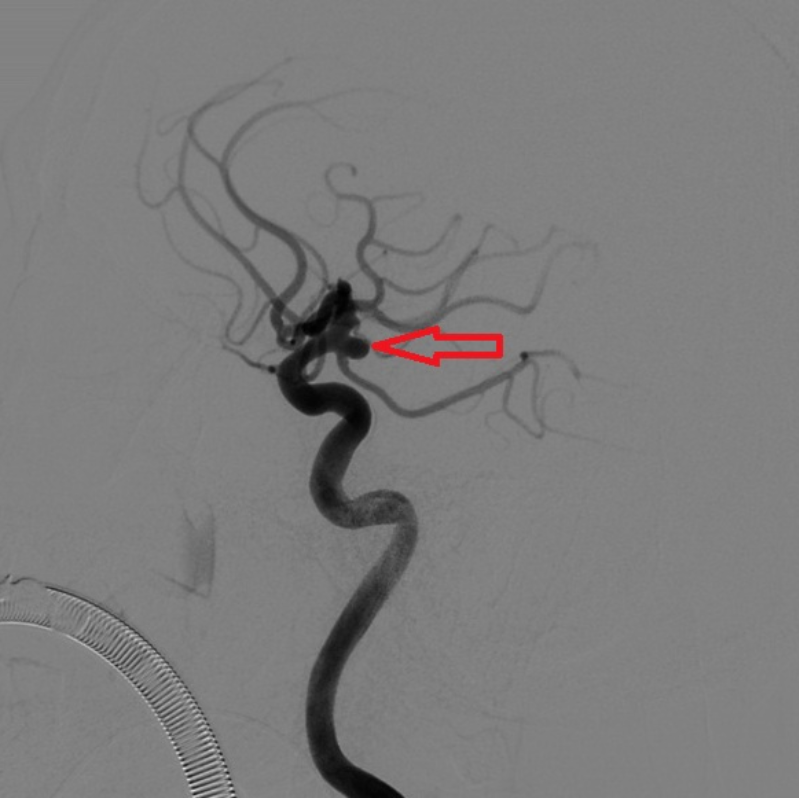

2024年3月30日,李某突然出現(xiàn)了劇烈的頭痛,隨即前往惠州市中心人民醫(yī)院博羅分院急診醫(yī)學(xué)科就診,急查頭部CT后發(fā)現(xiàn)是顱內(nèi)蛛網(wǎng)膜下腔出血!參與會診的神經(jīng)外科主治醫(yī)生曹繁明詳細(xì)地詢問了患者的病史,并做了詳細(xì)的神經(jīng)系統(tǒng)體格檢查,高度懷疑患者是顱內(nèi)動脈瘤破裂引起的蛛網(wǎng)膜下腔出血。急查了頭部CTA后發(fā)現(xiàn)了患者左側(cè)頸內(nèi)動脈C7段動脈瘤。

與此同時,另一名患者歐某,因如廁時摔倒頭痛就診,頭顱CT提示“蛛網(wǎng)膜下腔出血”,神經(jīng)外科副主任醫(yī)師李亞龍會診后完善血管CT檢查提示:“右側(cè)頸內(nèi)動脈C7段動脈瘤”,考慮蛛網(wǎng)膜下腔出血因動脈瘤破裂所致。

將患者收入神經(jīng)外科病房后,值班醫(yī)生詳細(xì)詢問了兩位病人的發(fā)病情況,仔細(xì)地做了體格檢查并閱讀了患者的頭部CTA,考慮他們的動脈瘤已經(jīng)破裂,如果再次破裂,后果極其嚴(yán)重,死亡率接近50%!為此,患者入院后,急診醫(yī)學(xué)科緊急聯(lián)系導(dǎo)管室,開啟 急診腦卒中綠色通道,在完善了腦血管造影術(shù)后(Digital subtraction angiography,DSA),兩位患者顱內(nèi)的動脈瘤及全部腦血管情況均已清楚地顯示了出來。